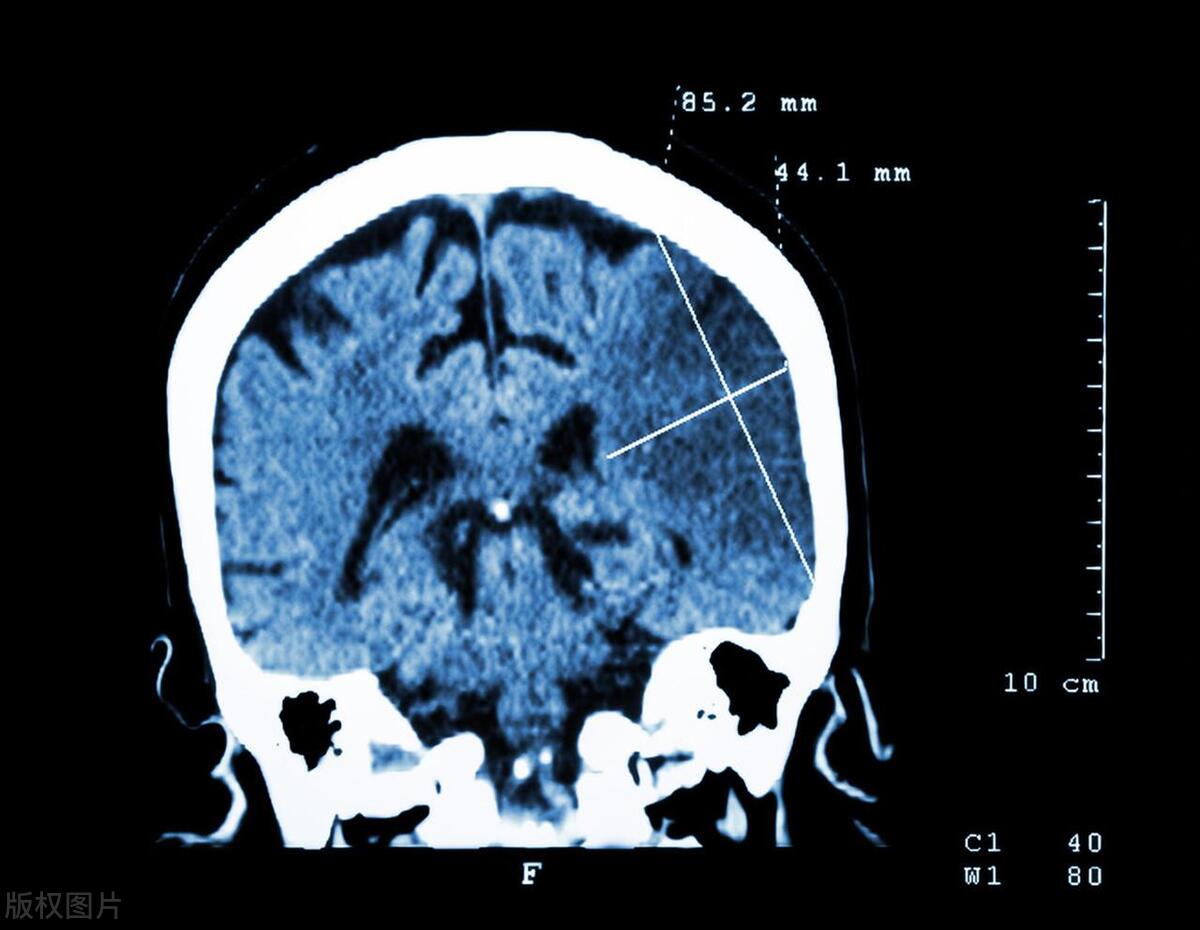

在转运过程中,对患者生命体征、病情变化进行密切关注,加强对患者生理指标监护,待送至医院后,立即为患者启动绿色通道,采用头颅 CT、核磁共振等影像学对患者实际情况及病情发展进行明确,以便进一步开展抢救措施,使用专门运送平车,以轻柔、平稳的方式将患者转运至抢救室,予以其吸氧、降低颅内压、纠正水电解质紊乱状况等常规治疗,维持血压稳定,同时,对患者进行血常规、凝血功能等相关指标检查,待经家属或本人同意并签署知情同意书后,予以患者颅内血管造影术、溶栓等相关治疗。